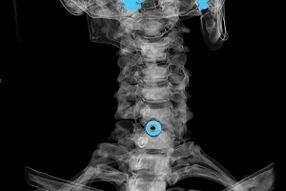

- Raios X. O método é ineficaz, principalmente nos últimos estágios do desenvolvimento da osteocondrose.

- Ressonância magnética (ressonância magnética) da coluna cervical. Um método que permite ver estruturas ósseas, hérnias de disco intervertebral, seu tamanho e direção de desenvolvimento.

- Tomografia computadorizada. Uma solução menos eficaz que a ressonância magnética, uma vez que a presença e o tamanho das hérnias são difíceis de determinar.